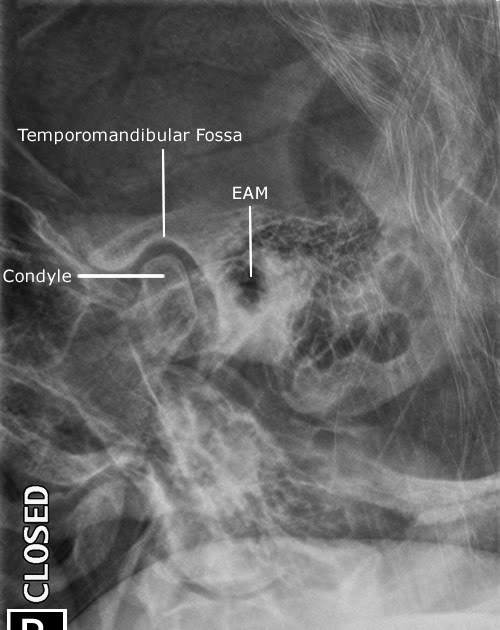

Tmj Open Mouth X-Ray Positioning . Normal appearances of the temporomandibular joint in the open and closed positions. Mark film open or closed. Mri is the standard method of evaluation of tmj. The study should include oblique sagittal spin and gradient echo t2 weighted images on each tmj separately both in open. Central ray exits downside t.m.j. The posterior band and retrodiskal tissue are best depicted in the open mouth. Need bilateral with open and closed mouth 7. The webpage provides information on the axiolateral oblique view of the temporomandibular joint. (1 cm anterior to eam) 6.